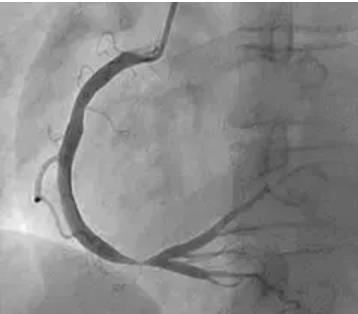

心血管介入诊疗技术